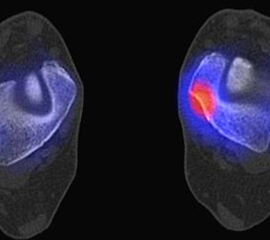

Die Abbildungen 4.2.a bis d zeigen den typischen Aspekt einer talacalcanearen Coalitio. Es besteht nur eine linksseitige, symptomatische Coalitio talocalcaneare (4.2.a und c); das 35 Tage zuvor angefertigte MRT zeigt keine auffälligen Signalveränderungen (4.2.b und d).

Abbildung 4.3. zeigt die Ursache für rechtsseitige Sprunggelenksbeschwerden bei einem Patienten mit talocalcanearen Coalitionen: nur die osteochondrale Läsion an der distalen rechten Tibia ist die Ursache des Schmerzes. Die bilateralen talocalcanearen Coalitionen sind asymptomatisch.